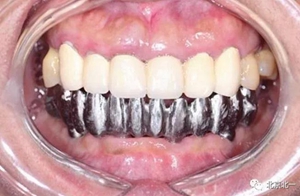

圖十八:口內(nèi)試戴鈦支架

圖十九:永久修復(fù)完成